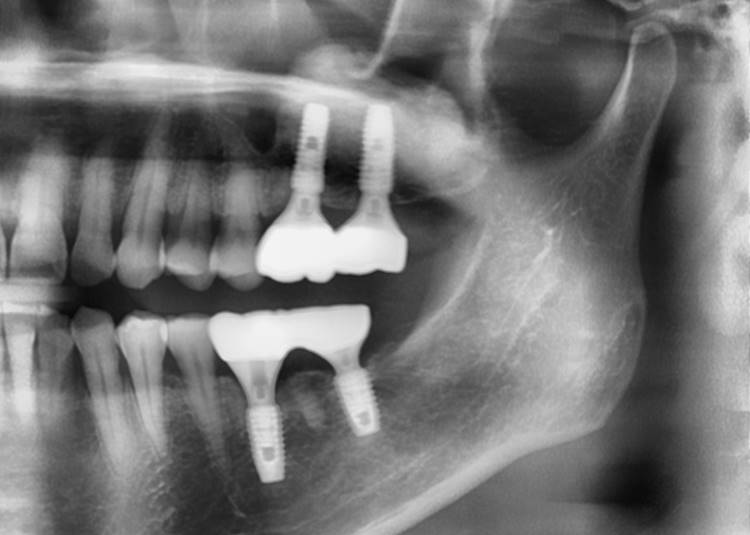

▲Panoramic radiograph before the implant surgery in the lower left area.

▲post-op panoramic radiograph.

▲. Panoramic radiograph after implant placement in the maxilla.(3 weeks after implant placement in the mandible)

▲Panoramic radiograph after 1 year of the crown delivery.